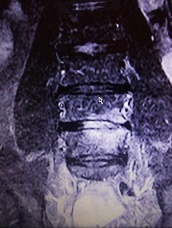

ich hatte vor kurzen ein Kontroll-MRT-LWS, weil bei mir eine Bandscheibenentzündung in DD oder eine Wirbelkörperentzündung. Im Bild im L4/5 ist dort etwas ungewöhnliches zu sehen, was kann das sein?

habe noch paar Bilder gefunden, die in der Sequenz T2W TSE sag; T1W TSE sag; TIR long TE cor

- Bild1.jpg (80.48 KiB) 6503 mal betrachtet

- Bild2.jpg (81.92 KiB) 6503 mal betrachtet

- Bild3.jpg (92.15 KiB) 6503 mal betrachtet

- Bild4.jpg (97.57 KiB) 6503 mal betrachtet

Das mit dem Kontroll-MRT kam auch nur von der HÄ, weil das ein Neurologe empfohlen hat. Weil voriges Jahr in der Stelle L4/5 eine Vermutung geäußert wurde, das im DD eine Diszitis vorliegt und das nach einem Jahr ein Verlaufs-MRT gemacht werden soll.